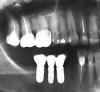

Несмеяна Опубликовано 3 февраля, 2010 Поделиться Опубликовано 3 февраля, 2010 Здравствуйте, уважаемые специалисты. Привожу в порядок рот. И возникли некоторые вопросы: Первый снимок: Как вы оцениваете состояние пломбирования нижней шестерки слева - я собираюсь ставить под нее коронку. Надо ли его перепломбировывать? Пломба там во весь зуб, стенки тонкие. Второй снимок: На верхней шестерке справа хочу поменять коронку (сейчас стоит штампованная и она сместилсь). Можно ли не проходить каналы - зуб резрциненный, не болит. Просто врач говорит проходить надо, но без гарантии, а цена вопроса минимум 15 тыр. Может лучше просто одеть кронку за 7 тыс. без той же гарантии и пусть стоит зубик? А потом когда-нибудь имплант? Скажите, как лучше поступить? И еще вопрос по поводу каналов - 2 сверху - надо перлечивать? Можно ли оставить зуб, наложив винир или лучше убрать под коронку. Какую коронку лучше поставить на передний зуб, чтоб не чернела десна?И еще подскажите, 3 - снизу - нормально залечен, стоит ли его тоже заново лечить? Может еще у меня есть какие-то проблемы, которые заметны по снимку и требуют срочного решения?Заранее благодарна Ссылка на комментарий

Polikarp Опубликовано 3 февраля, 2010 Поделиться Опубликовано 3 февраля, 2010 (изменено) Здравствуйте, уважаемые специалисты. Привожу в порядок рот. И возникли некоторые вопросы: Первый снимок: Как вы оцениваете состояние пломбирования нижней шестерки слева - я собираюсь ставить под нее коронку. Надо ли его перепломбировывать? Пломба там во весь зуб, стенки тонкие. Второй снимок: На верхней шестерке справа хочу поменять коронку (сейчас стоит штампованная и она сместилсь). Можно ли не проходить каналы - зуб резрциненный, не болит. Просто врач говорит проходить надо, но без гарантии, а цена вопроса минимум 15 тыр. Может лучше просто одеть кронку за 7 тыс. без той же гарантии и пусть стоит зубик? А потом когда-нибудь имплант? Скажите, как лучше поступить? И еще вопрос по поводу каналов - 2 сверху - надо перлечивать? Можно ли оставить зуб, наложив винир или лучше убрать под коронку. Какую коронку лучше поставить на передний зуб, чтоб не чернела десна?И еще подскажите, 3 - снизу - нормально залечен, стоит ли его тоже заново лечить? Может еще у меня есть какие-то проблемы, которые заметны по снимку и требуют срочного решения?Заранее благодарнаОбратите внимание на пришеечную область нижней 6-ки,не изменена ли она в цвете? Изменено 3 февраля, 2010 пользователем Polikarp Ссылка на комментарий

Polikarp Опубликовано 3 февраля, 2010 Поделиться Опубликовано 3 февраля, 2010 нижнюю шестерку немногие возьмутся переделывать,а если возьмутся-то без гарантии,т.к. скорее всего это резорцин-формалин без гуттаперчи,распломбировать будет очень сложно,на корнях все в порядке,но если полезть в него и не доделать до конца,последствия могут быть самыми разными.За такой зуб возьмется или классный эндодонт с большим кол-вом времени,или энтузиаст стоматологии. Самое забавное,что если бы доктор в каналы 36 зуба вставил-бы хотябы по 1 гуттаперчевому штифту 25 размера,все доктора исключили-бы зуб из списка на "перелечивание" Ренальд в чем-то прав по поводу красивых картинок Ссылка на комментарий

Polikarp Опубликовано 4 февраля, 2010 Поделиться Опубликовано 4 февраля, 2010 Мое мнение по поводу нижней шестерки-аккуратно удаляем анкер,т.к. около его основания мне не нравится структура зуба,далее стекловолоконный штифт вместо анкера и непрямая композитная вкладка-оверлей(с перекрытием всей поверхности).Категорически лично мое видение.Многие со мной не согласятся. Ссылка на комментарий